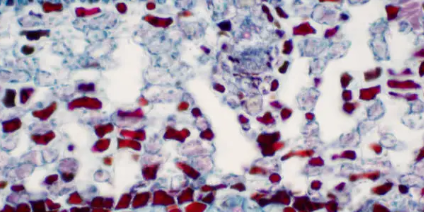

다형홍반의 진단은 주로 임상적으로 이루어지며, 피부 병변의 특징적인 외관과 환자의 병력을 기반으로 합니다. 그러나 진단을 확정하기 위해서는 두드러기, 혈관염, 약물 반응 등 유사한 증상을 가진 다른 질환을 배제하는 것이 필요할 수 있습니다. 피부 생검은 다른 피부 질환을 배제하고, EM과 일치하는 조직학적 특징(예: 표피 괴사 및 혈관 주위 염증)을 평가하는 데 유용할 수 있습니다.

EM에서는 면역 시스템의 반응이 감염이나 약물에서 유래된 항원에 대한 것으로, 이로 인해 염증의 연쇄 반응이 발생합니다. EM에서 보이는 표적 병변은 이러한 염증 과정의 결과로, 면역 세포가 피부에 침입하여 표피와 진피에 손상을 일으킵니다. 표적 병변의 특징은 괴사 세포 사멸과 염증 반응을 반영하는 것으로 여겨집니다.